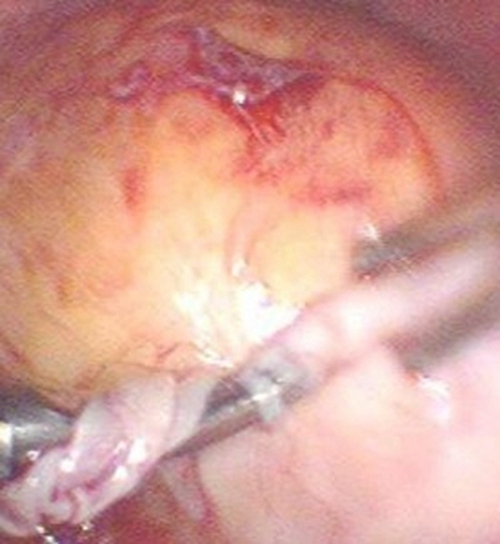

手術後巧克力囊腫

手術後巧克力囊腫的

A:巧克力囊腫如果是直徑>5cm,有手術指徵就需要做手術。一般選擇微創的手術腹腔鏡,把卵巢的巧克力囊腫剝除,術後還要給予長期的規範化管理,否則巧克力囊腫很容易就復發。當巧克力囊腫很小的時候,直徑巧克力囊腫又叫子宮內膜異位囊腫,它的發病原理是由……

A:巧克力囊腫是子宮內膜異位症的一種,會引起進行性加重的痛經,囊腫會隨著時間的推移,逐漸增大,症狀逐漸加重,治療以手術為主,有腹腔鏡和開腹手術方法。具體費用和手術方式、耗材、醫院級別有關係,如果囊腫沒有出現扭轉或者破裂等,手術操作相對簡單,一般……